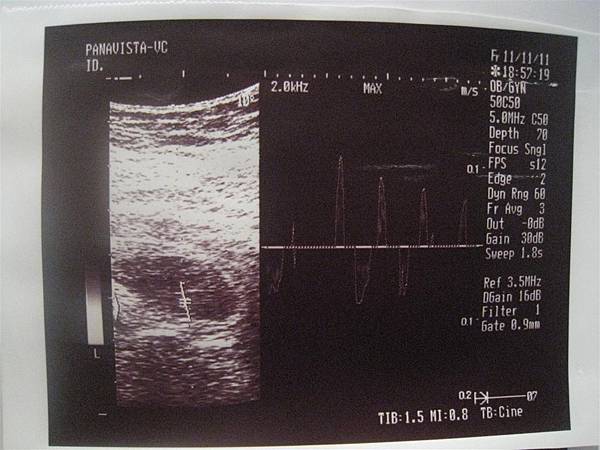

100.11.11 確定聽到心跳,拿到第二本媽媽手冊了唷~